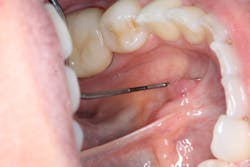

Clinical assessment reveals a red, tissue-colored, raised, fluctuant mass on the left side of the lingual frenum, in the area of the submandibular gland duct. There is a slight tenderness to palpation with some firmness to the lesion overall. The mass measures approximately 4 mm x 5 mm in length (see photos below).